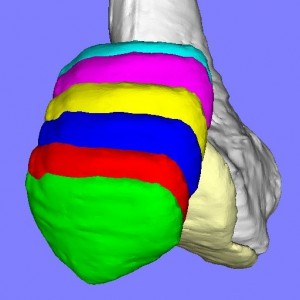

膝蓋骨脱臼には様々なパターンがあり、患者それぞれの膝蓋骨の動きのパターンを評価して適切な手術方法を検討します。

膝蓋骨の動きには上図のように様々なパターンが存在します。(我々の研究結果から)